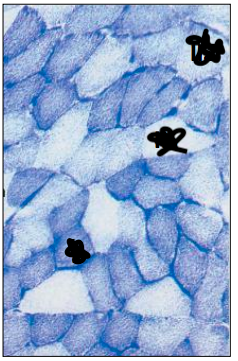

What is represented by the C and N in the skeletal muscle image below

C – capillary

N - nucleus